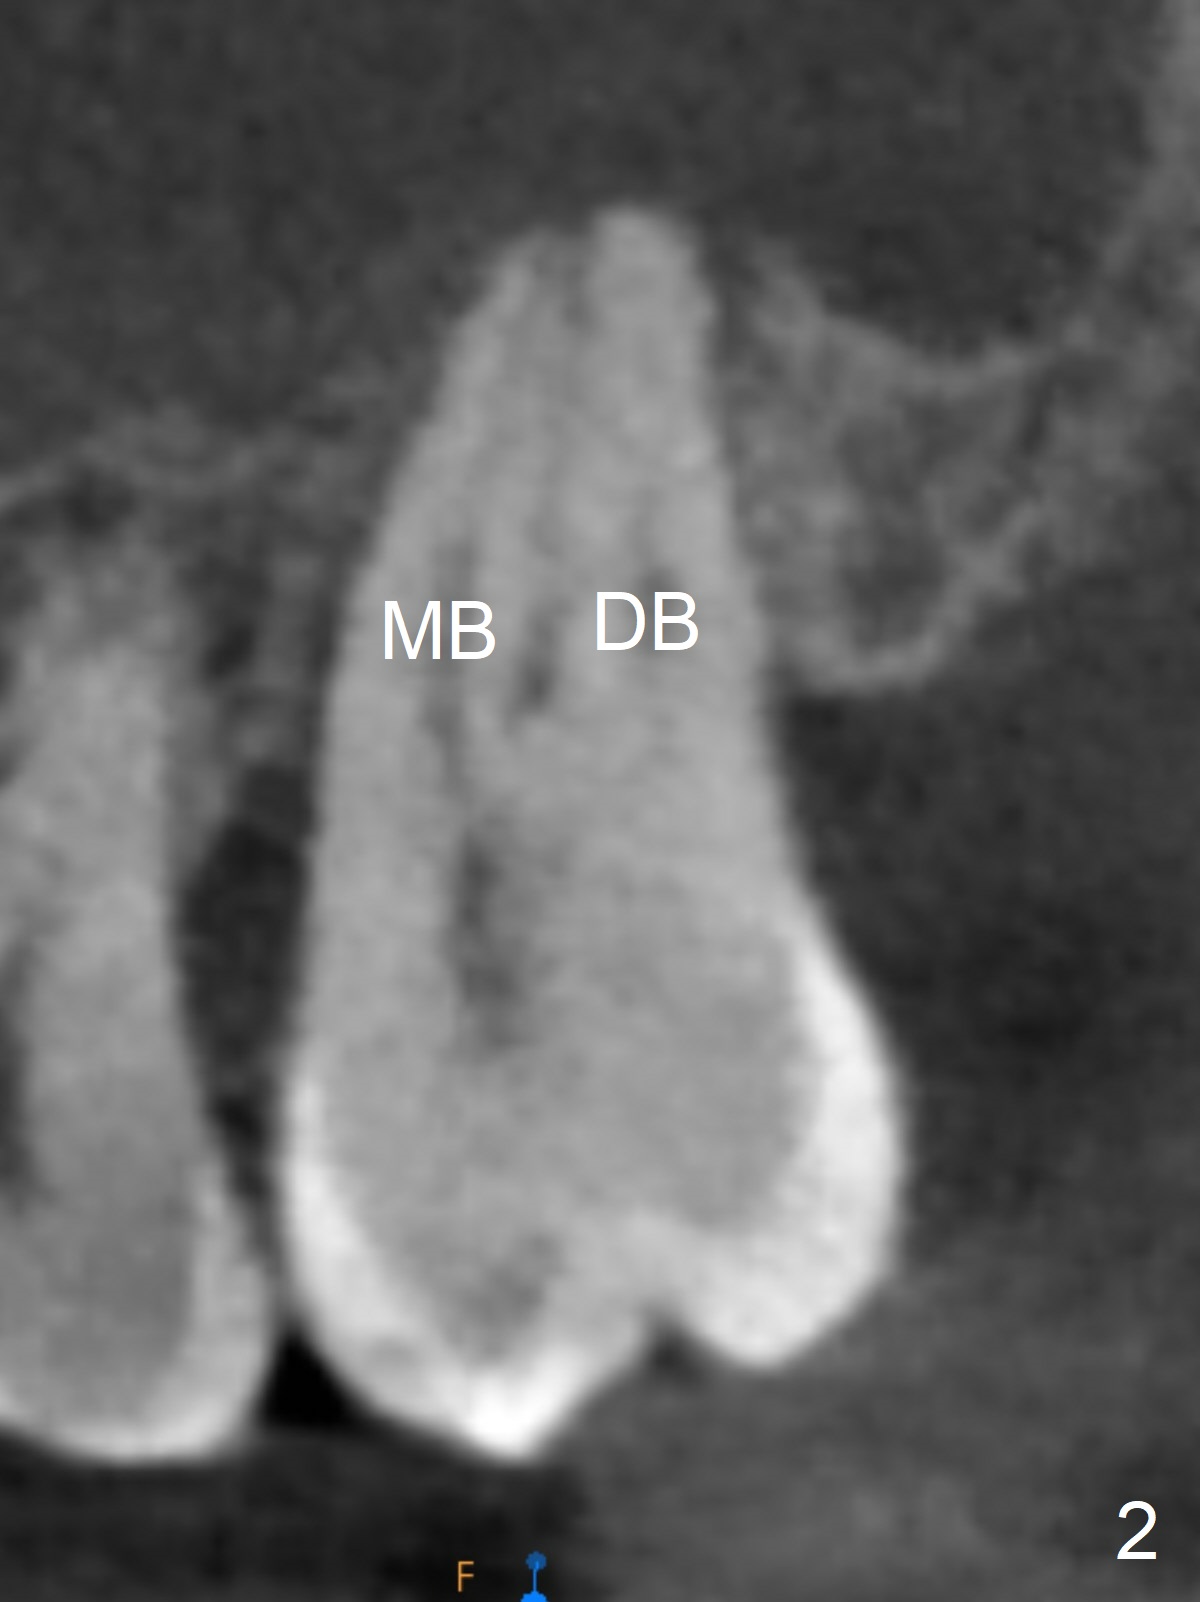

A 40-year-old man develops an abscess around the buccal roots of the tooth #15 several years after extraction of the symptomatic tooth #16. The pattern of infection is similar to that between #17 and 18. There is severe bone loss (Fig.1 *) around the fused buccal roots (Fig.2). It appears that an immediate implant (green) placed in the septum (Fig.4) has better position and angulation for restoration than the one placed in the palatal socket (Fig.3). Pink: cuff of abutment (blue); yellow: Osteogen Plug; red: bone graft.